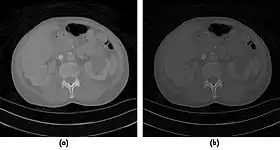

CT Fluoroscopy

- CT Fluoroscopy (CTF) has also been referred to as Continuous CT or Real-Time CT since it involves generating tomographic images at sufficiently high frame rates to allow guidance of needle placement in small or deep-seated lesions. Applications can include biopsy of thoracic lesions, biopsy/drainage of pelvic lesions, vertebroplasty and drainage/aspiration of intracranial haematomas. The advantages of CTF include increased target accuracy and reduced procedure times[45].

- The value of N is typically 30o, 45o or 60o, with frame rates of 12, 8 and 6 frames per second, respectively. In the case of 60o updates and 6 frames per second, the delay between each image is 0.17 seconds. A Last-Image-Hold (LIH) technique can be used while the image is being updated with the resulting time lag being considered by the interventionist in terms of biopsy technique. Example images are shown in Figure 7.15.11. The display of three adjacent slices of thickness 5 mm with MDCT scanning can be used to improve visual feedback to the interventionist as the needle progresses. In addition, multi-planar reconstructions (MPR) and volume rendered 3D images can be used to enhance fine control.